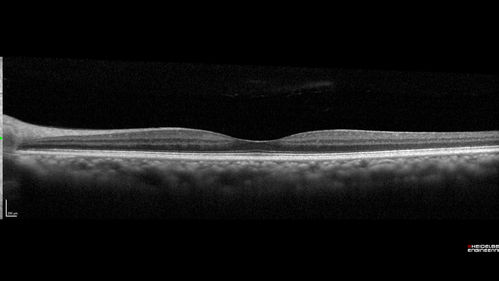

Macroaneurysm - Macular Hemorrhage - Branch Retinal Aterial Occlusion

62 year old African American female with chronic hypertension and vision loss for 2 weeks. VA is 20/400

Macroaneurym - Fresh Macular Hemorrhage - branch retinal arterial occulsion distal to MA